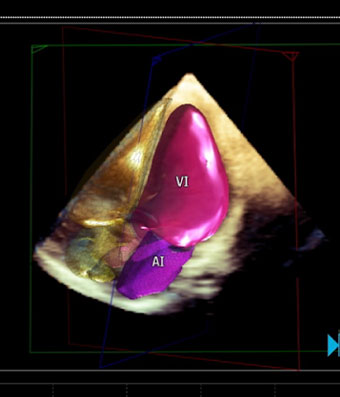

Ecocardiografía

El ecocardiograma o ecocardiografía utiliza ondas sonoras de alta frecuencia para obtener imágenes del corazón en vivo y que son proyectadas en una pantalla. Este auxiliar diagnóstico aporta información en 30 a 60 minutos de la forma, tamaño, función y movimiento del corazón así como de sus estructuras internas, como por ejemplo las válvulas cardiacas. Este estudio es seguro en pacientes adultos, en pacientes pediátricos (ecocardiograma pediátrico) o incluso en mujeres embazadas para estudiar el desarrollo del corazón del bebé en la cavidad uterina (ecocardiografía fetal).

Las imágenes ecocardiografías del corazón pueden ser obtenidas en diferentes modos (unidimensional, bidimensional o tridimensional, Doppler, Doppler color), utilizando una sonda externa (ecocardiograma transtorácico) o una sonda interna (ecocardiograma transesofágico) y puede ser adquirido en reposo, en estrés con esfuerzo físico o con el uso de medicamentos (estrés con dobutamina), dependiendo del diagnóstico y de la indicación de tú médico.